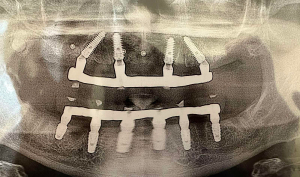

Зубні імпланти з титану приживаються у ротовій порожнині пацієнта із вірогідністю 98%. Технологія імплантації повністю змінилася за останні кілька років, і тепер вони пропонують міцність і пожиттєву гарантію.

Імплантація вирішує проблему пацієнтів з повною адентією (повна втрата зубів). За допомогою постановки 4 або 6 імплантатів, можна повернути функцію і естетику повність беззубої щелепи за технологією «all on 4» або «all on 6». В нашій клініці ми використовуємо лише високоякісні системи імплантів, котрі дають надійний результат на довгі роки.